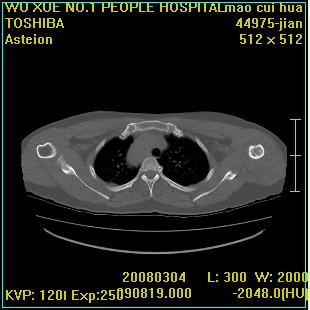

标题: CT12025:男,50岁,左肩活动受限半年。 [打印本页]

标题: CT12025:男,50岁,左肩活动受限半年。

肩关节骨质破坏呈小囊状,其周软组织轻度肿胀,余未见异常。

考虑:肩袖损伤。建议mri。

左侧肱骨头密度不均匀,高低混杂,周围软组织略肿胀,考虑结核性病变。

左侧肱骨头密度不均匀,高低混杂,髓腔密度稍高,周围软组织略肿胀,肌间隙模糊,考虑慢性骨髓炎可能。密切结合临床!